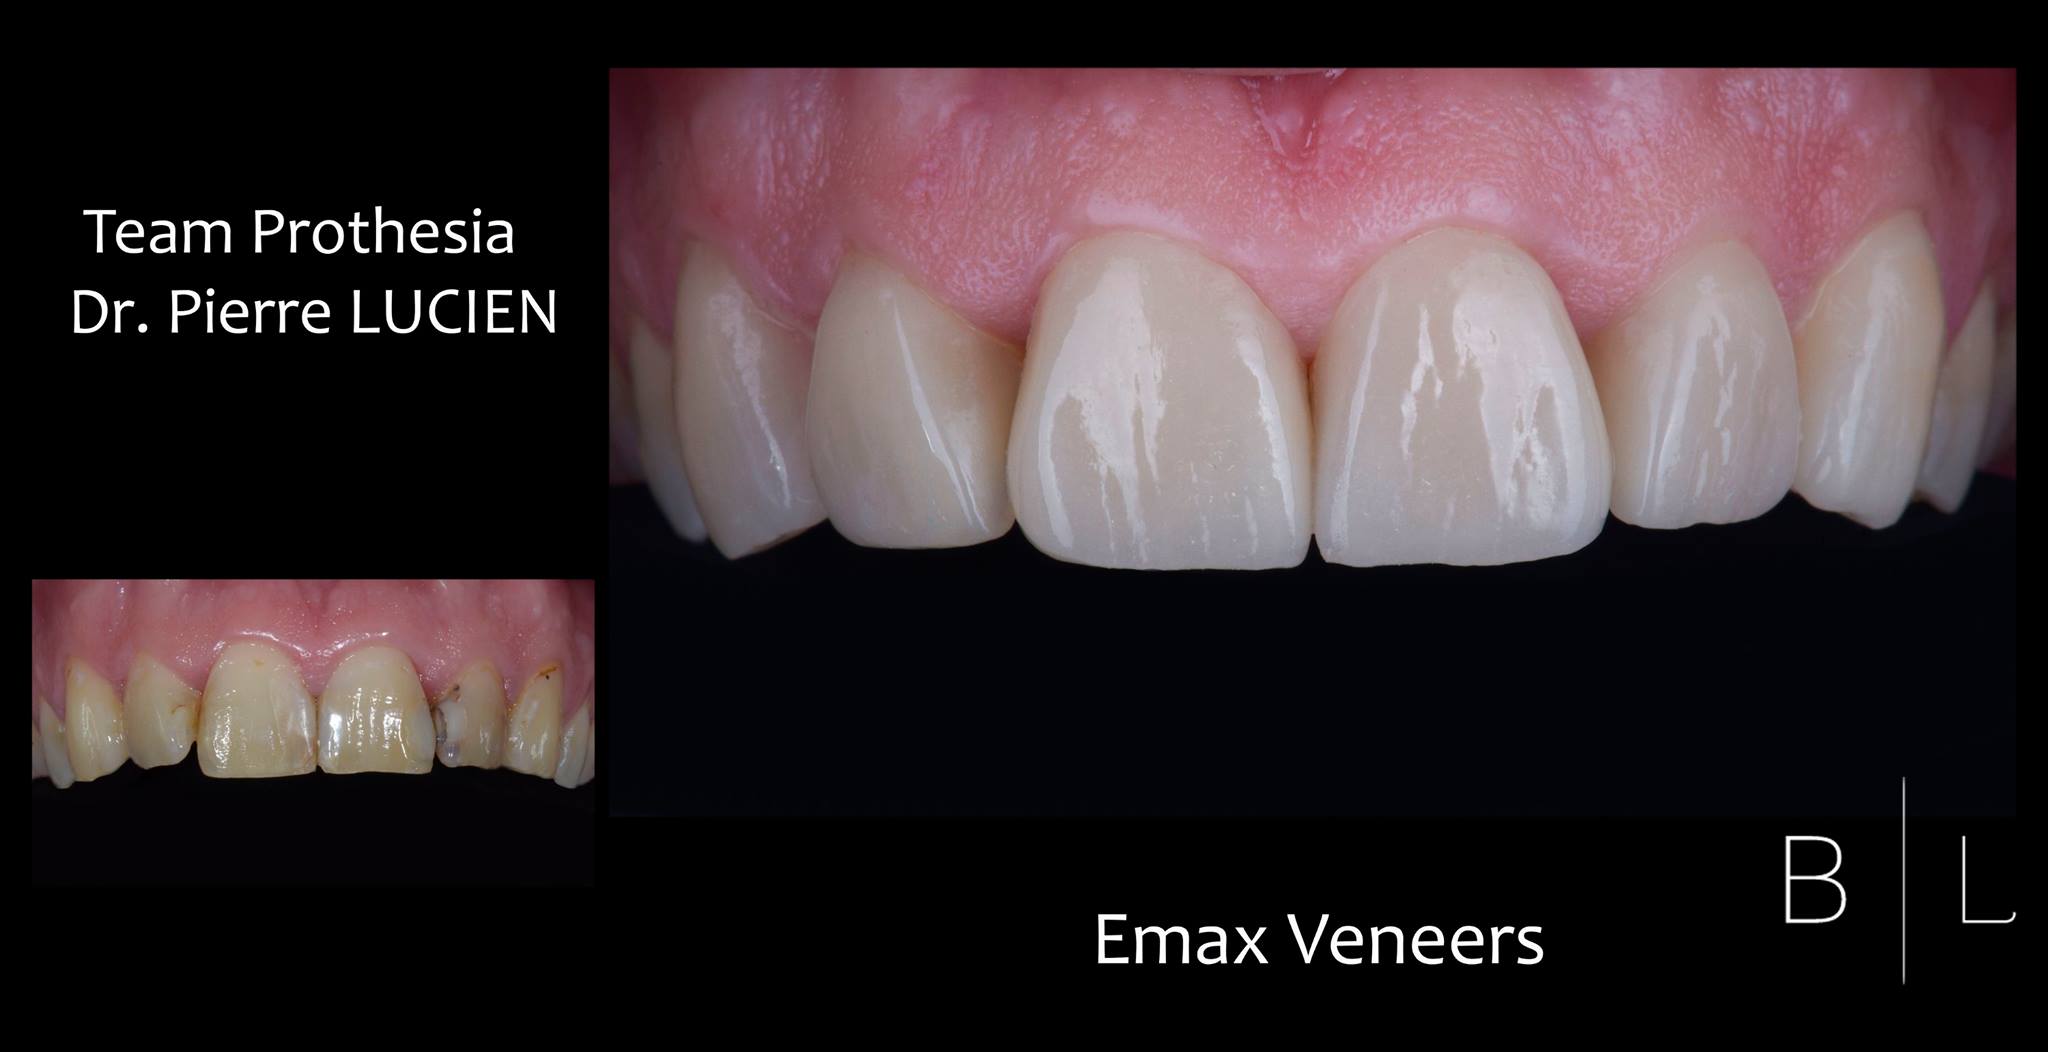

Facettes 11-21

Emax by Team Prothesia - Surgery and Restorative by Dr Bensoussan #ditramax #veneers #DSD #newsmile #BL

Facettes - E max -Antibes